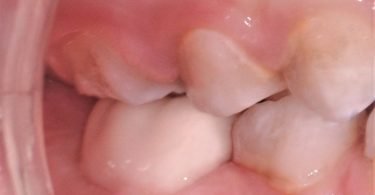

Foi realizado um exame clínico e radiológico inicial (fig. 1 a 3), tendo sido diagnosticada, entre outras lesões de cárie, uma lesão de cárie profunda com atingimento pulpar no segundo molar temporário inferior direito (fig. 3). Foi proposta a realização de uma pulpotomia com agregado trióxido mineral (MTA) e a colocação de uma coroa pré-formada. As várias possibilidades restauradoras foram apresentadas e discutidas com os pais, que decidiram optar pela colocação de uma coroa pré-formada de zircónia, por motivos estéticos.